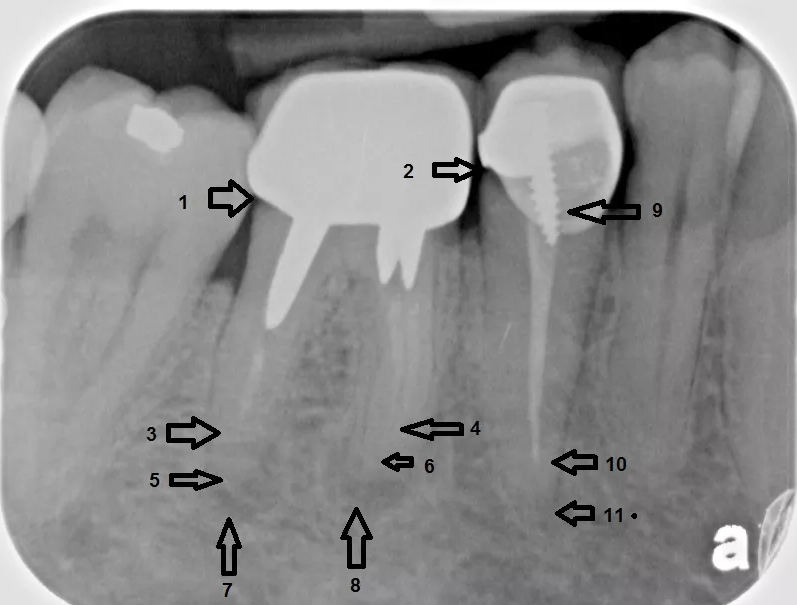

치근단부 종양이 확인되는 X선 사진

근관 치료 엑스레이 사진

9번이 교두(cusp), 15번이 근단공(apical foramen)이다.

근관장(working length)이란 근관 치료의 작업 길이를 뜻하며 근관 치료의 범위를 결정하는 기준이 된다. 근관장은 치아의 교두정(cusp tip)에서 근단공(apical foramen)의 가장 좁은 부위까지의 거리를 말하며, 근관장을 본래의 길이보다 짧게 측정시 나머지 부분의 세균을 제거하지 못하고, 길게 측정시 기구가 근관의 끝 이상을 넘어가 치주조직에 손상이 가해진다.[133]

X-ray explanation of bad root canal therapy

조잡한 근관 치료의 엑스레이 사진

근관 치료의 또 다른 흔한 합병증은 근관 전체를 완전히 깨끗하게 청소하고 근관 충전재(보통 거타퍼차)로 채우지 못했을 때 발생한다. 반면에, 근관 충전재가 치근단에서 밀려나와 다른 합병증을 유발할 수도 있다. 위 그림의 엑스레이는 잘못된 근관 치료를 받은 인접한 두 개의 치아를 보여준다. 근관 충전재(3, 4 및 10)는 치아 뿌리(5, 6 및 11) 끝까지 확장되지 않는다. 치아 뿌리 하단의 어두운 원(7 및 8)은 주변 뼈의 감염을 나타낸다. 권장되는 치료법은 근관 치료를 다시 하거나 치아를 발치하고 임플란트를 식립하는 것이다. 불량한 품질의 충전재 또는 밀봉재도 근관 치료 실패의 원인이 될 수 있다.[46]